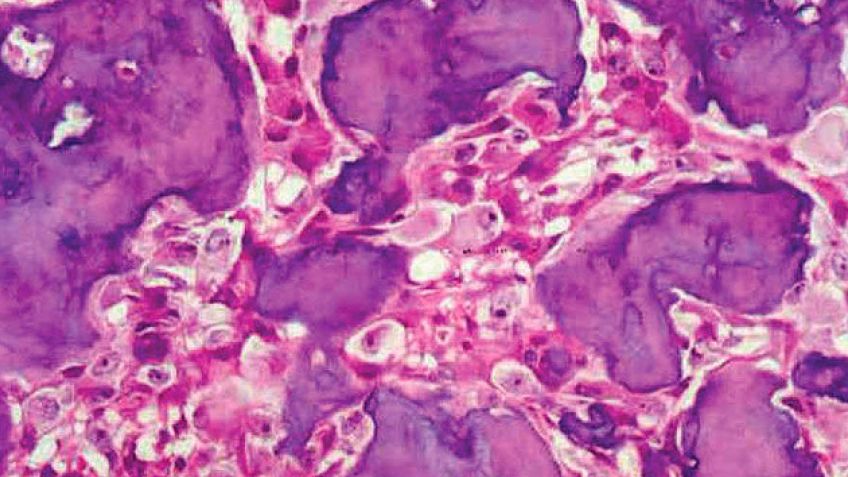

Según refiere la Cleveland Clinic de Estados Unidos el osteoblastoma es "un tumor, por lo general benigno, que sin embargo puede causar dolor e inflamación". El tumor óseo incrementa las chances de que el paciente afronte fracturas o cualquier tipo de lesión en la zona. Los tratamientos incluyen cirugía para extirpar la masa del cuerpo. Cabe destacar que luego de la intervención quirúrgica algunos osteoblastomas pueden volver a emerger, especialmente si el cirujano no logró una práctica capaz de eliminar la totalidad del tumor.

Cuando el tumor óseo crece, ataca las regiones sanas y crea un osteoide, es decir, un nuevo tejido. Aunque puede aparecer en cualquier parte del cuerpo, lo más común es que lo haga en la columna vertebral -como aparentemente es el caso de Iglesias-, manos y piernas. Es poco frecuente, emerge principalmente en los hombres y se estima que tan solo representa el 3 por ciento de los tumores benignos diagnosticados. Alonso plantea al respecto: "La mayor parte de los casos se ven en la columna vertebral y su evolución puede ser muy disruptiva para la persona. Genera deformidad, compresión y dolor".